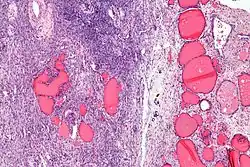

| Micrograph of a struma ovarii. Characteristic thyroid follicles are seen on the right, and ovarian stroma on the left. H&E stain. | |

Low magnification -

Higher magnification